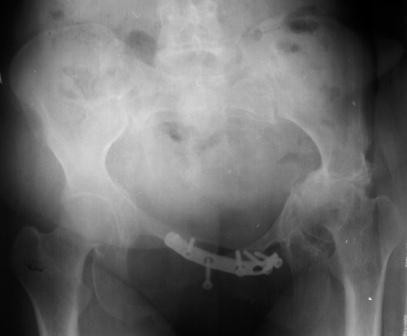

Уважаемые коллеги! Пациентка 32 года с застарелым повреждением таза, после остеосинеза лонного сочленения пластиной. Посоветуйте с выбором тактики и методик лечения.

Получила травму в феврале 2004г в г.Лобытнанги ЯНАО Тюм.обл. Через неделю после поступления выполнен остеосинтез лонного сочленения пластиной. 1,5 месяца на скелетном вытяжении. В последующем ходит при помощи костылей с нагрузкой на правую ногу. Имеется нестабильность половин таза, неправильно-консолидированный перелом левой вертлужной впадины, невропатия седалищного нерва слева. В результате невропатии седалищного нерва сформировалась эквинусная установка левой стопы,парестезии по подошвенной поверхности.

Клинически: ходит на костылях с нагрузкой на правую ногу. Левая стопа в эквинусе. Осевая нагрузка на левую н\конечность болезненна в области левого тазобедренного сустава, при прикосновениях к подошвенной поверхности стопы у пациентки чувство зжения. В левом коленном суставе полный обьем движений, в левом тазобедренном резко ограничено отведение и ротация, укорочение левой н\конечности на 2,5 см. При полипроекционной и функциональной Р-графии выявлена нестабильность левого КПС и лонного сочленения, консолидированный в порочном положении поперечный оскольчатый перелом левой вертлужной впадины с центральным смещением головки бедра. Нами выполнена коррекция деформации левой стопы. Планируется выполнить введение 2 канюлированных илиосакральных винтов слева, реостеосинтез лонного сочленения реконструктивной пластиной, после заживления ран - тотальное эндопротезирование левого тазобедренного сустава.